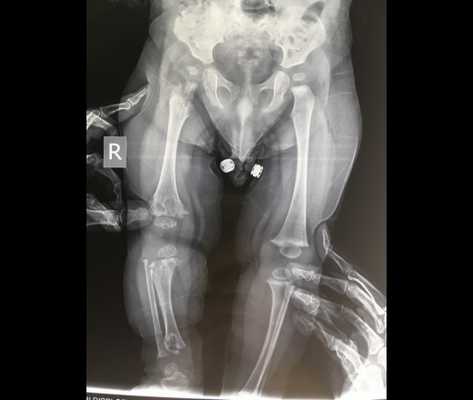

Клиническая картина включает в себя: неполное разгибание в локтевом суставе, килевидную грудную клетка, искривление ног, удлинение малоберцовой кости относительно большеберцовой. У больных наблюдаются укорочение и утолщение кистей, разболтанные суставы кистей и стоп, недоразвитые ногти. При рентгенологическом исследовании выявляются изменения, названные метафизарным дизостозом: расширенные метафизы с фестончатым, неровно склерозированным краем. Биопсия выявляет гипоплазию хрящей. Волосы у больных тонкие, короткие, редкие, светлые. Поражаются также брови и ресницы. У многих больных имеются иммунологические дефекты, нарушается как клеточный, так и гуморальный иммунитет. Они чувствительны к инфекциям, могут иметь лимфопению, нейтропению, анемию. У некоторых больных нарушается кишечное всасывание, а также у них повышен риск опухолеобразования, преимущественно лимфом.

Отмечается внутриутробное отставание в росте. Конечности короткие, в основном укорочены кисти и стопы, пальцы короткие и толстые. В некоторых случаях отмечаются небольшое искривление нижних конечностей, генерализованная разболтанность суставов, подвывих или вывих головки лучевой кости. Волосы, брови и ресницы редкие, тонкие и светлые. При этом заболевании могут наблюдаться анемия, нарушение всасывания в кишечнике, снижение клеточного иммунитета.

Осложнениями синдрома являются артриты, килевидная деформация грудной клетки вследствие раннего закрытия швов грудины и эквиноварусные деформации стоп. К характерным рентгенологическим признакам относится расширение метафизов в области коленных суставов и средних фаланг кистей и стоп, а также умеренное уплощение и недоразвитие тел позвонков (у взрослых эти изменения исчезают).

Метафизарная хондродисплазия (хряще-волосяная гипоплазия, СНН; тип Мак-Кьюсика, MIM 250250) - форма карликовости с короткими конечностями, возникающей в результате скелетной дисплазии. Скелетные особенности включают неполное разгибание в локтевом суставе, килевидная грудная клетка, искривление ног, удлинение малоберцовой кости относительно большеберцовой. У больных наблюдаются укорочение и утолщение кистей, разболтанные суставы кистей и стоп, недоразвитые ногти. При рентгенологическом исследовании выявляются изменения, названные метафизарным дизостозом: расширенные метафизы с фестончатым, неровно склерозированным краем. Биопсия выявляет гипоплазию хрящей. Волосы у больных тонкие, короткие, редкие, светлые. Поражаются также брови и ресницы. У многих больных имеются иммунологические дефекты, нарушается как клеточный, так и гуморальный иммунитет. Они чувствительны к инфекциям, могут иметь лимфопению, нейтропению, анемию. У некоторых больных нарушается кишечное всасывание, а также у них повышен риск опухолеобразования, преимущественно лимфом.

Метафизарная хондродисплазия Мак-Кьюсика (гипоплазия хряща и волос) - редкое заболевание, которое является причиной карликовости. У пациентов наблюдается сильное укорочение конечностей (до 20 см), что связано с дисплазией скелета.

Для пациентов с типом MакКьюзика характерны хроническая анемия, патологии кишечника. На рентгеновских снимках заметно увеличение метафизов в области коленного сустава. В детском возрасте нередко встречается двояковыпуклое строение позвонков, которое постепенно исчезает после взросления.